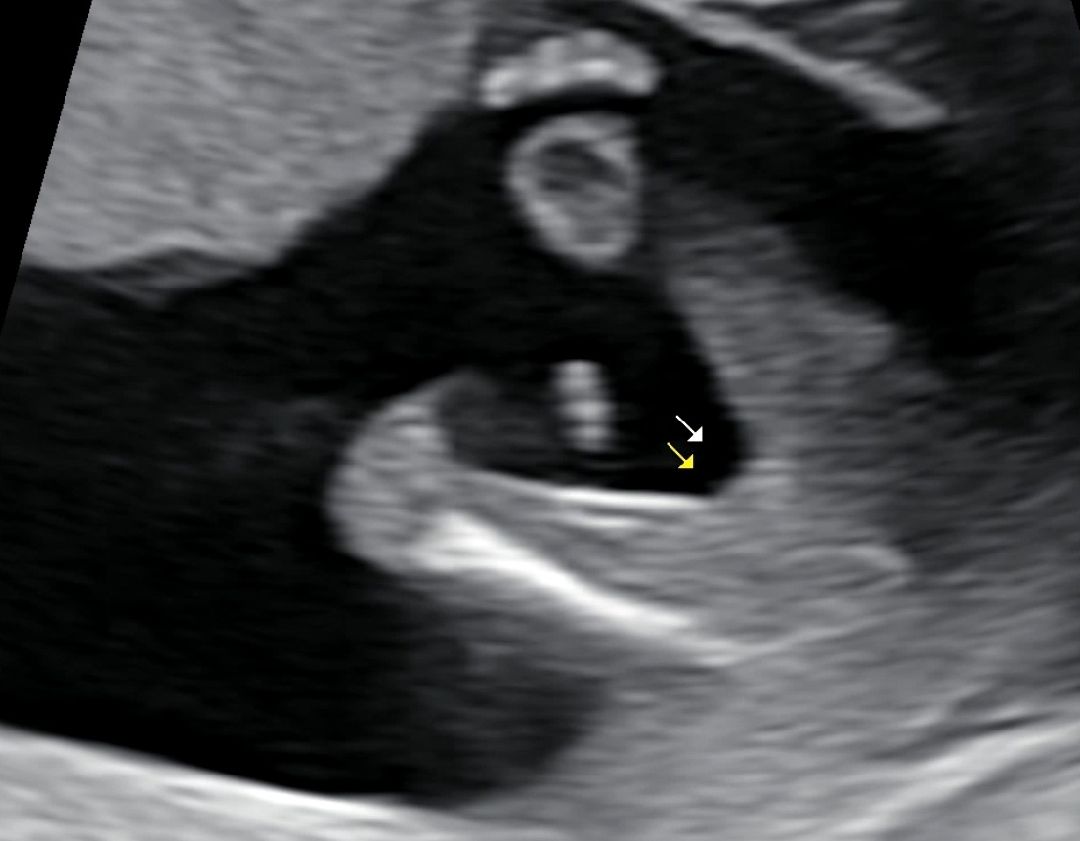

14주차인데 오늘 아기 보러 갔는데 의사선생님이 공주인것같아~ 말하셨어요 ㅎㅎ 혹시 나중에 아들로 반전 될 수 있을까요? 남편이 너무 신나서 볼안해요 ㅎㅎ

아뇨아뇨! 저건 무조건 딸이에요 축하드려요🍑